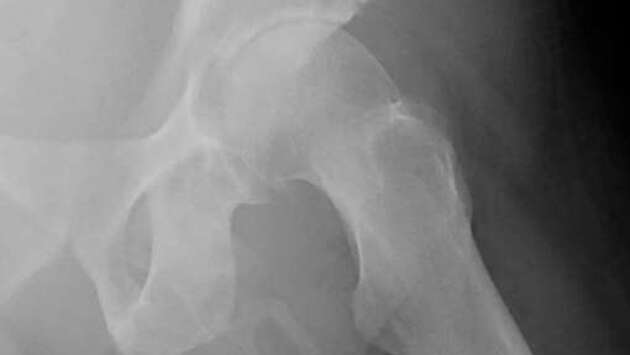

Мужчина из США рассказал, что его пенис превращается в кость из-за редкого заболевания, пишет LADBible. По словам американца, изменения в органе начали происходить после того, как он упал на улице. Как сообщают СМИ, 63-летний мужчина обратился в больницу Нью-Йорка с жалобами на боль в левом колене после падения на тротуар. Пациента отправили на рентген, потому что врачи подозревали у него возможный перелом в бедренной кости, что и могло быть причиной дискомфорта. Однако вместо перелома врачи обнаружили нечто гораздо более необычное – у мужчины образовалась "внескелетная кость" в пенисе. По словам специалистов, эта костеподобная кальцификация накапливалась в мягких тканях вдоль пениса американца, делая его твердым, как кость. Сам процесс простыми словами называется окостенением полового члена и является чрезвычайно редким заболеванием, которое наблюдается менее чем у 40 человек в мире. Сам пациент рассказал медикам, что иногда испытывает боли в пенисе, но никогда не придавал этому значения. Врачи рекомендовали ему дальнейшее обследование и лечение, однако он решил покинуть больницу без дальнейшего наблюдения.